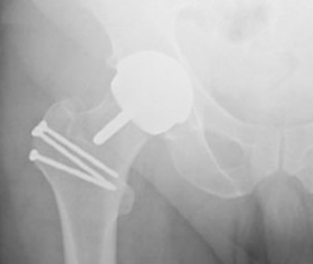

Partial Hip Replacement

Doctors recommend partial hip replacements (hemiarthroplasty) when only one part of a hip

needs treatment. In most cases, the acetabulum, also known as the socket or cup, remains intact and a ball replaces the head of the femur. Some partial hip replacements only address the

acetabulum. A partial hip replacement typically corrects a hip fracture at the neck of the femur.